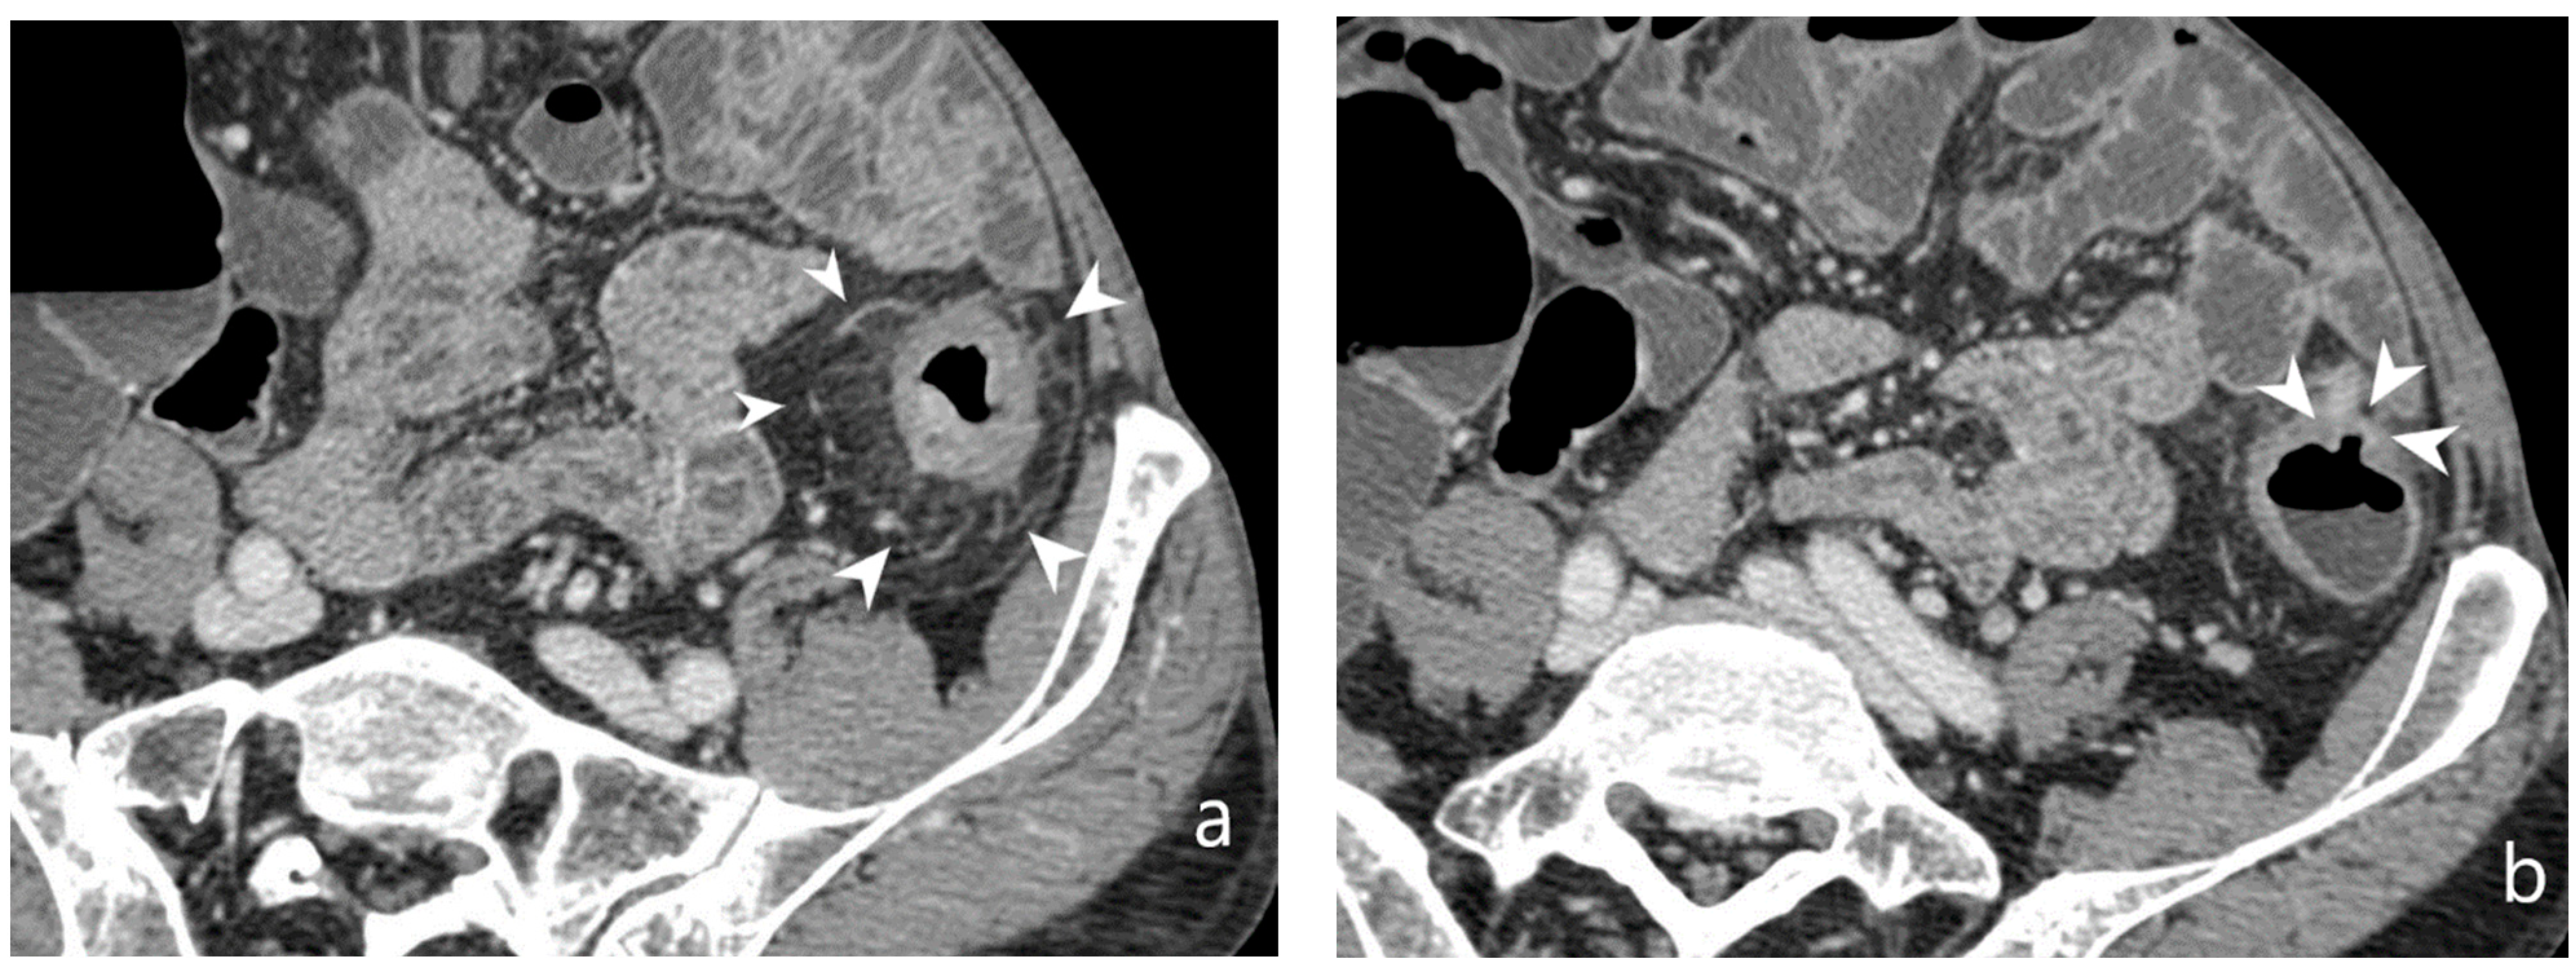

5.3. Fistulising/Perforating Subtype